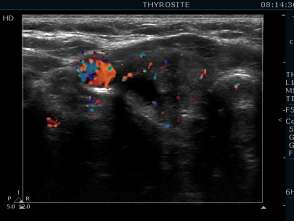

First session of the sclerotherapy (second row of images):

Clinical presentation: the patient had no complaints.

Hormonal investigation indicated subclinical hyperthyroidism (TSH 0.02 mIU/L, FT4 17.4 pM/L).

Ultrasonography: the nodule in the right lobe significantly increased.

Suggestion: definitive therapy. The patient chose ethanol sclerotherapy.

Five sessions of ethanol was administered. We gave 13 mL ethanol in all.